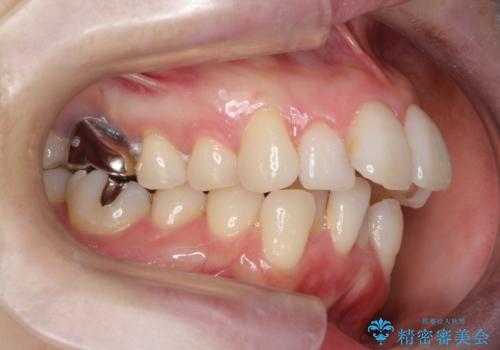

重度のガタガタと出っ歯をワイヤーによる抜歯矯正で整った歯並びへ

- 全体的ながたがたを主訴に来院されました。

上顎の前歯は前方に傾斜して、下顎の前歯は強いガタガタが見られました。

前から4番目の歯を上下左右合計2本抜歯して、歯並びを整える計画としました。

ワイヤー矯正にて治療しました。